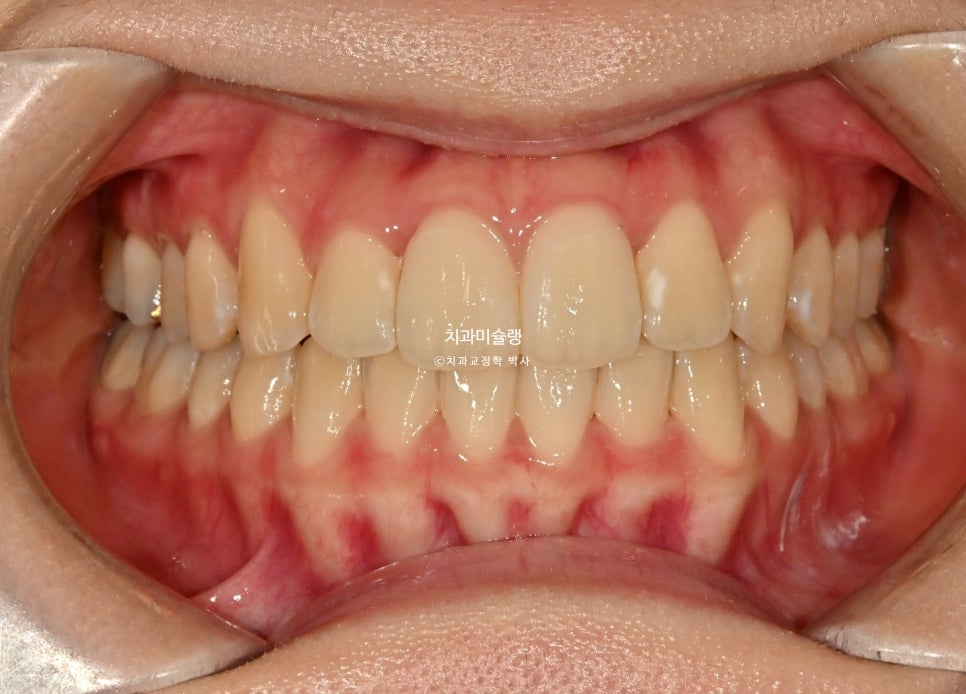

치료 완료 후 결과

중심선은 잘 맞으며

어금니 교합관계는1급이고 잘 물립니다.

토탈 치료기간은 1년 6개월, 재제작은 1회 했습니다.

앞니가 뒤로 들어가며 약간의 돌출감이 해소되었죠.

깔끔해진 스마일라인과

적절한 앞니각도

과하지 않게 들어간 입술

앞니가 뒤로 들어가면 입이 좀더 편하게 다물립니다.